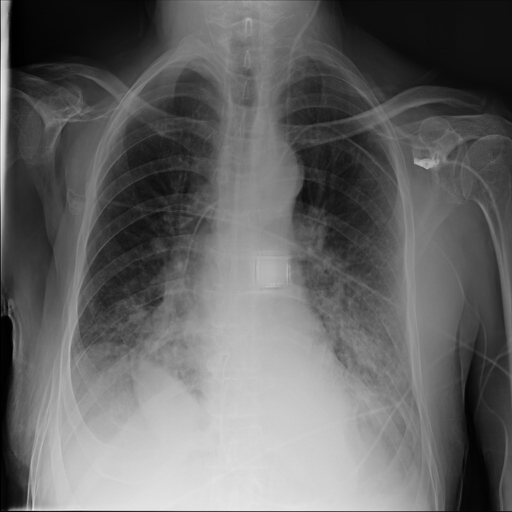

Refer to caption

(a) Original

case 1

(b) ϵ=103HWitalic-ϵsuperscript103𝐻𝑊\epsilon=10^{3}\cdot H\cdot W

(c) ϵ=102HWitalic-ϵsuperscript102𝐻𝑊\epsilon=10^{2}\cdot H\cdot W

(d) ϵ=101HWitalic-ϵsuperscript101𝐻𝑊\epsilon=10^{1}\cdot H\cdot W

(e) Original

case 2

(f) ϵ=103HWitalic-ϵsuperscript103𝐻𝑊\epsilon=10^{3}\cdot H\cdot W

(g) ϵ=102HWitalic-ϵsuperscript102𝐻𝑊\epsilon=10^{2}\cdot H\cdot W

(h) ϵ=101HWitalic-ϵsuperscript101𝐻𝑊\epsilon=10^{1}\cdot H\cdot W

(i) Original

case 3

(j) ϵ=103HWitalic-ϵsuperscript103𝐻𝑊\epsilon=10^{3}\cdot H\cdot W

(k) ϵ=102HWitalic-ϵsuperscript102𝐻𝑊\epsilon=10^{2}\cdot H\cdot W

(l) ϵ=101HWitalic-ϵsuperscript101𝐻𝑊\epsilon=10^{1}\cdot H\cdot W

(m) Original

case 4

(n) ϵ=103HWitalic-ϵsuperscript103𝐻𝑊\epsilon=10^{3}\cdot H\cdot W

(o) ϵ=102HWitalic-ϵsuperscript102𝐻𝑊\epsilon=10^{2}\cdot H\cdot W

(p) ϵ=101HWitalic-ϵsuperscript101𝐻𝑊\epsilon=10^{1}\cdot H\cdot W

Figure 2: ϵitalic-ϵ\epsilon-LDP-processed CXR images obtained with DP-GLOW.

In Fig. 1, we show four ϵitalic-ϵ\epsilon-LDP-processed CXR images of clinical cases obtained with the image domain LDP, which directly imposes the Laplace mechanism on the input image, with different privacy budgets together with the original images. Fig. 2 shows four ϵitalic-ϵ\epsilon-LDP-processed CXR images of clinical cases obtained with DP-GLOW and different privacy budgets together with the original images. In case 1 for DP-GLOW, there is decreased permeability in the bilateral hilar regions. Although this hilar opacity tends to be preserved with a larger privacy budget, the entire image is degraded when the privacy budget becomes 101HWsuperscript101𝐻𝑊10^{1}\cdot H\cdot W. A similar tendency is observed in the images of all the four cases for DP-GLOW; for example, in case 4 with ϵ=101HWitalic-ϵsuperscript101𝐻𝑊\epsilon=10^{1}\cdot H\cdot W, the lung opacity suggesting pneumonia in the right lower lung field is well preserved, while the entire image is degraded.